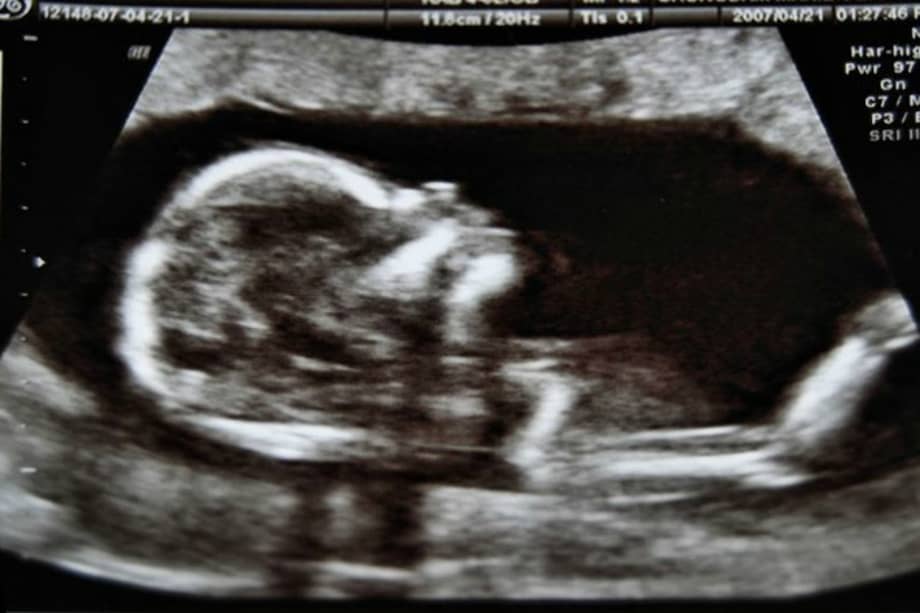

“Debido al papel crucial de la placenta en el apoyo al desarrollo del feto y al actuar como interfaz con el entorno externo, la presencia de partículas plásticas potencialmente dañinas es una cuestión de gran preocupación. Es necesario realizar más estudios para evaluar si la presencia de microplásticos puede desencadenar respuestas inmunitarias o puede conducir a la liberación de contaminantes tóxicos, lo que resulta en daños”, escribieron los científicos italianos en la revista Environmental International tras demostrar la presencia de microplásticos en la placenta humana.

Para el experimento, los científicos encabezados por Antonio Ragusa del departamento de Ginecología del Hospital San Giovanni Calibita Fatebenefratelli, en Roma, recolectaron seis placentas de mujeres que dieron su consentimiento y luego las analizaron usando una técnica de microspectroscopía aplicada con éxito en el campo biomédico, para caracterizar tanto muestras biológicas como para detectar la presencia de microplásticos y micropartículas en general. Los microplásticos son partículas de menos de cinco milímetros derivadas de la degradación de los objetos plásticos presentes en el medio ambiente.

En total, los científicos encontraron 12 fragmentos microplásticos (de 5 a 10 μm de tamaño), de forma esférica o irregular, en 4 placentas tanto del lado fetal como del materno. Las partículas fuerona analizadas y se confirmó que estaban pigmentadas. Tres fueron identificados como polipropileno teñido, un polímero termoplástico, mientras que para los otros nueve solo fue posible identificar los pigmentos, que fueron todos utilizados para revestimientos artificiales, pinturas, adhesivos, yesos, pinturas para dedos, polímeros y cosméticos y productos de cuidado personal..

Más allá de los riesgos para la salud humana, aún desconocidos, lo importante es que con este trabajo se confirma que los humanos hemos causado un impacto tan grande sobre el ambiente y los ecosistemas que hasta uno de los lugares más recóndito de nuestra naturaleza, la placenta humana, está siendo invadida por estos materiales artificiales.

“Es como tener un bebé cyborg: ya no está compuesto solo de células humanas, sino de una mezcla de entidades biológicas e inorgánicas”, dijo Ragusa, director de obstetricia y ginecología del hospital San Giovanni Calibita Fatebenefratelli en Roma, a medios de comunicación.

¿Cómo están llegando los microplásticos hasta las placentas humanas? Se cree que los microplásticos entrarían al torrente sanguíneo de la madre desde el sistema respiratorio materno o el tracto gastrointestinal. Células en ambos sistemas podrían “comerse” estas partículas y conservarlas dentro de sí. Los científicos creen que después de efectuarse este primer mecanismo, los microplásticos viajarían a otros órganos del cuerpo por cuenta de respuestas inflamatorias e inmunológicas.

“Una vez que los microplástios han llegado a la superficie materna de la placenta, como otros materiales exógenos, pueden invadir el tejido en profundidad mediante varios mecanismos de transporte, tanto activos como pasivos, que aún no se comprenden con claridad”, escribieron.